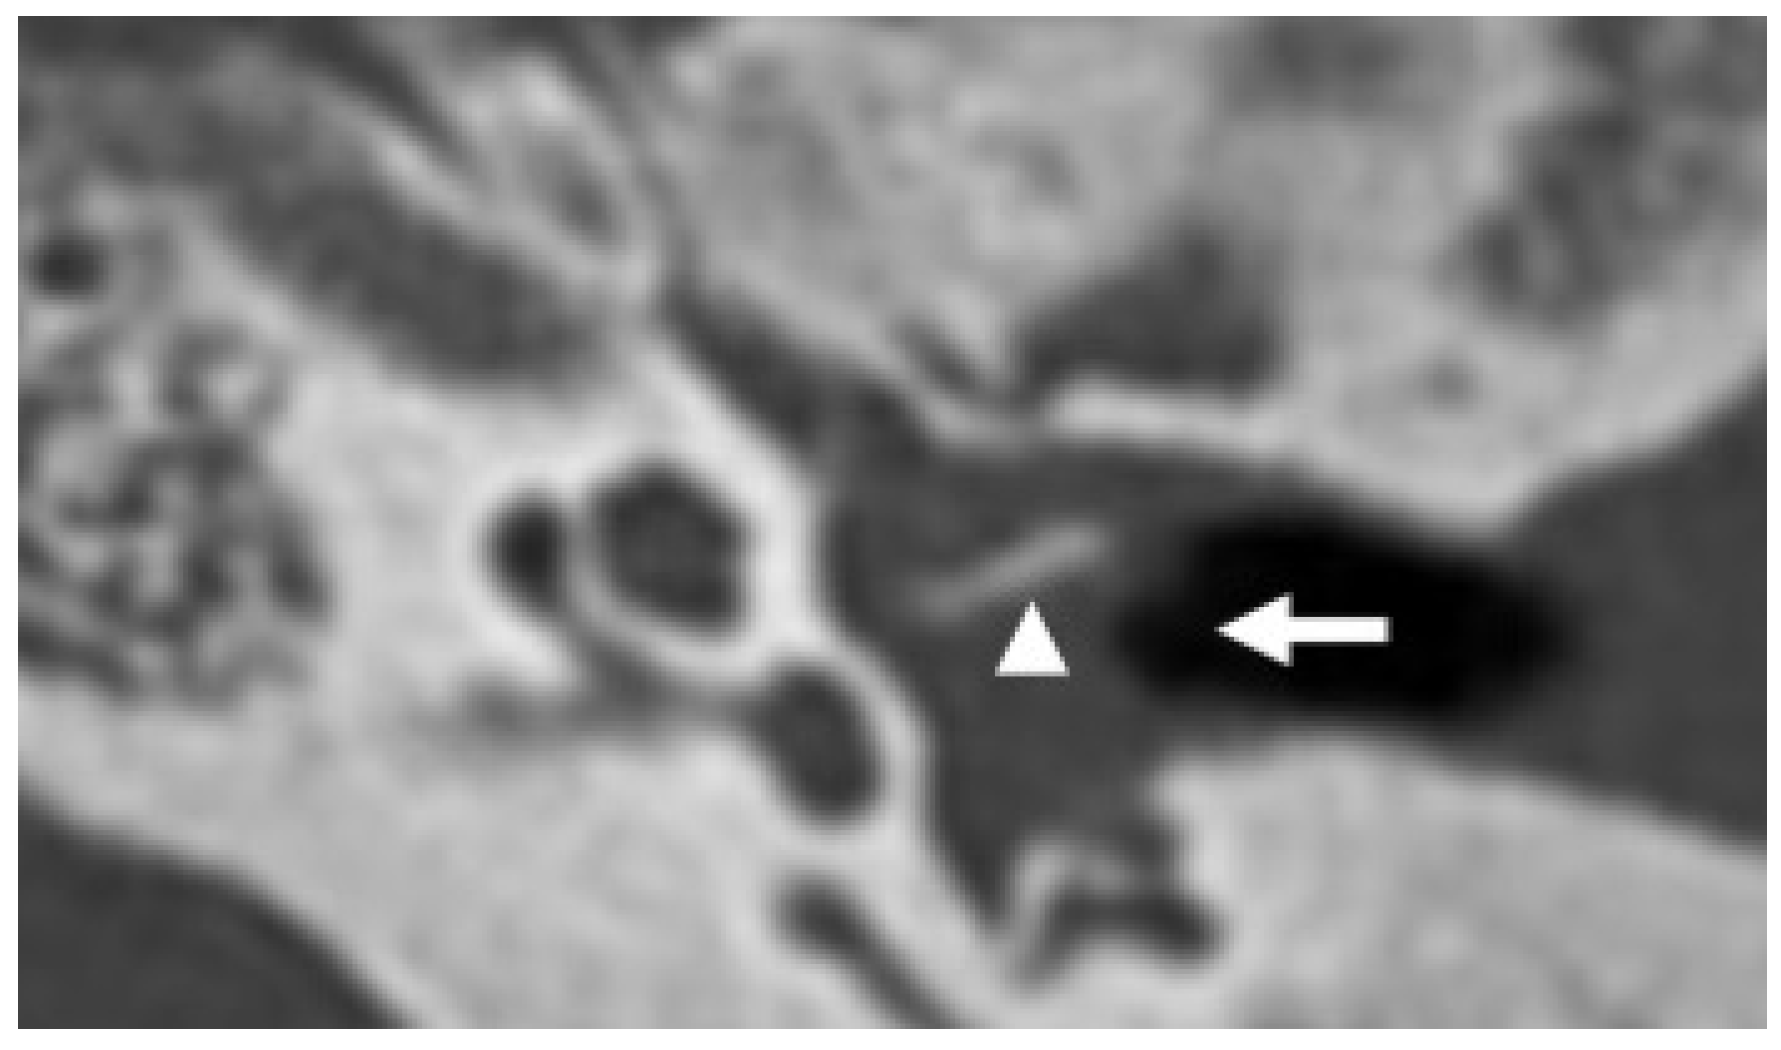

3.2. Bony Dehiscence

| Bony Dehiscence/Temporal Bone Defects | Barbara et al., 2022 [22]; Sanna et al., 2009 [23]; Lim et al., 2012 [24]; Rabiei et al., 2025 [25] | Case-based studies and reviews | Tegmen tympani or semicircular canal defects create a route for meningitis and meningoencephalocele; HRCT coronal reconstructions preferred. |